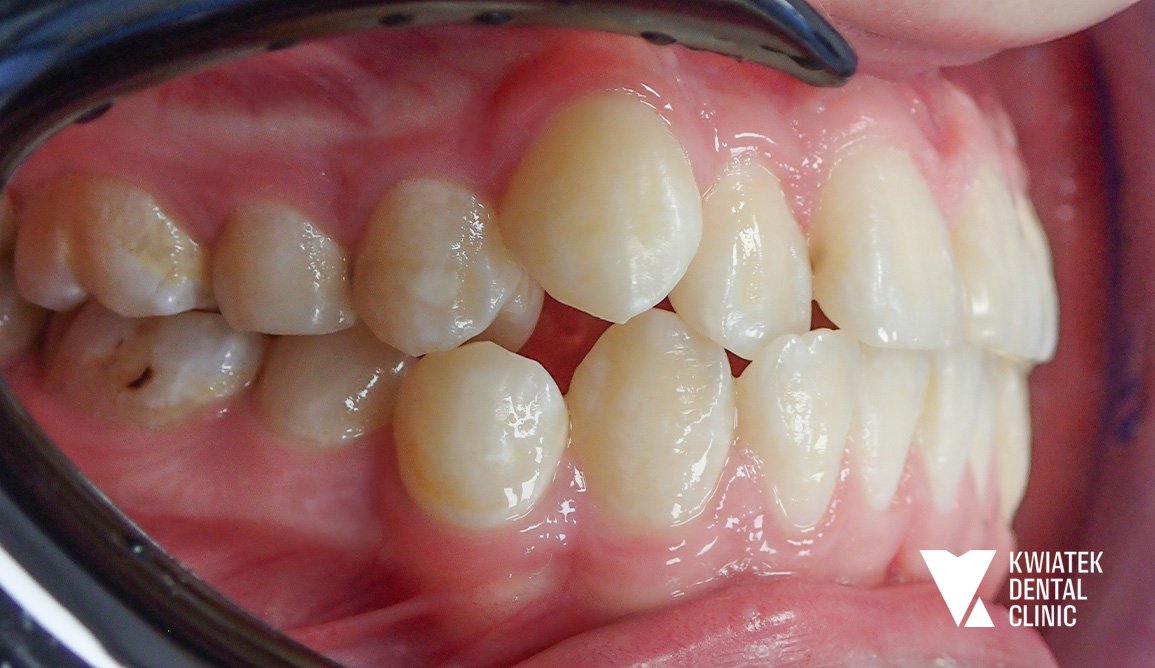

Pełna rekonstrukcja zwarcia i estetyki - historia wymagającej metamorfozy

Pacjent zgłosił się do kliniki z zaawansowanymi problemami stomatologicznymi: licznymi ubytkami próchnicowymi, brakami zębowymi, starciem zębów oraz zaburzeniami zwarcia. Leczenie obejmowało kompleksową diagnostykę, leczenie zachowawcze i endodontyczne, zabiegi chirurgiczne, implantację oraz wieloetapową odbudowę protetyczną. Efektem terapii jest perfekcyjnie zbalansowany zgryz, najwyższy komfort funkcjonowania oraz naturalnie piękny uśmiech, który podkreśla indywidualny charakter pacjenta i pozwala mu w pełni cieszyć się nim każdego dnia.